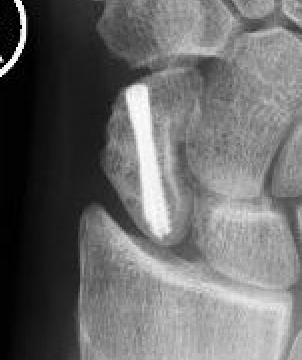

Percutaneous screw fixation

Indications

Minimally displaced fracture in acceptable position

Manual workers / athletes - limit time in cast

- meta-analysis of dorsal v volar percutaneous scaphoid fixation

- no difference in outcomes

Volar percutaneous screw technique

Vumedi volar percutaneous screw video

Dorsal percutaneous screw technique

Vumedi dorsal percutaneous screw video